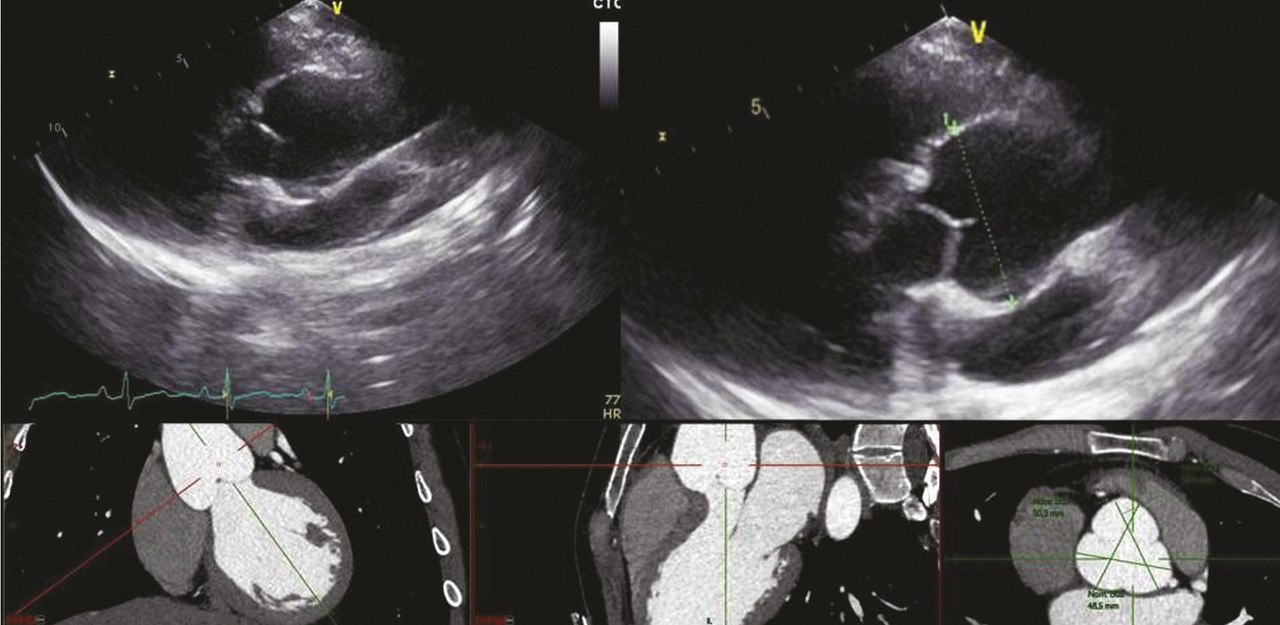

Sur le plan cardiovasculaire, le syndrome de Marfan se traduit principalement par une atteinte de la paroi aortique. La dilatation aortique prédomine au niveau des sinus de Valsalva dont le diamètre progresse en moyenne de 0,5 mm/an dans l’ensemble de la population Marfan adulte (mais chez certains patients la dilatation s’opère moins vite que chez d’autres). Le risque de dissection au niveau de l’aorte ascendante est corrélé au diamètre maximal au niveau des sinus de Valsalva (fig. 1 ). Cela justifie une surveillance des diamètres aortiques tous les ans, tout au long de la vie, même lorsque les diamètres sont dans les valeurs normales. Cette surveillance est généralement réalisée par échocardiographie et, chez les patients adultes, on confirme au moins une fois la fiabilité des mesures échographiques par une autre technique (généralement une tomodensitométrie injectée) [fig. 2 ].